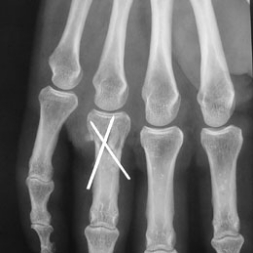

A - Radiographie de face des doigts : Brochage croisé pour fracture de la base de la premiére phalange.

Contrôle d'un brochage phalangien.